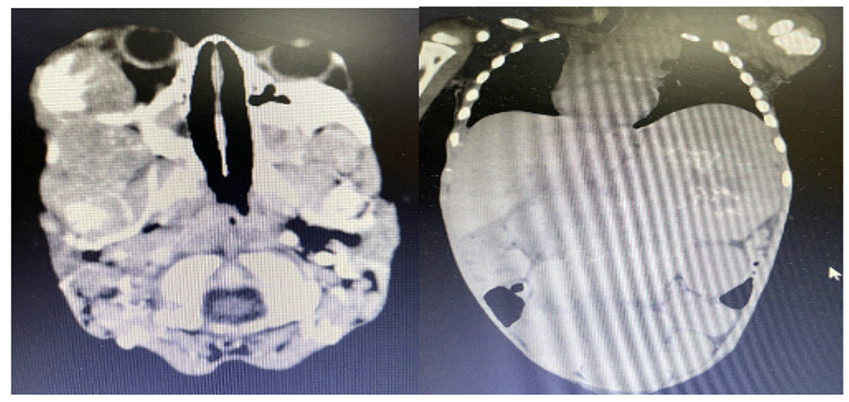

Given the advanced stage of the tumor and the systemic and neurological deterioration, the patient was treated with chemotherapy. However, despite supportive therapies, the disease progressed rapidly in a short period of time, suggesting unusual aggressiveness in the presence of infection (Figures 1–4).

Figures 1 and 2 CT scan of the skull and abdomen and pelvis showing neuroblastoma infiltration.